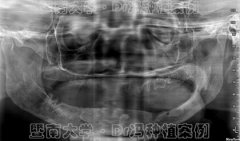

1年换4副假牙的书法家1天“长”新牙 专家解读这

一年换了4副假牙,都抵不上5颗种植牙!七旬书法家曾令校14年前就开始掉牙,活...【详细】

【健康报】暨南大学口腔种植医生赖仁发:一位

从医行医,悬壶济世,尽力尽心尽责治病救人,不求富贵,不寻奢华,不追显赫...【详细】